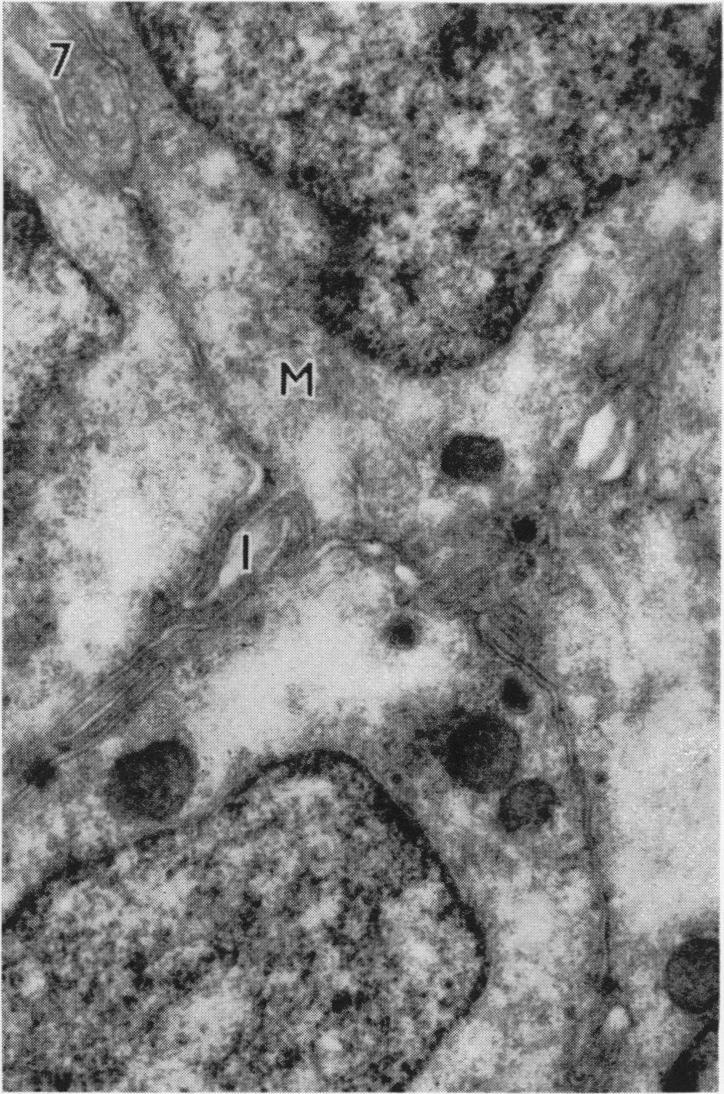

AN ELECTRON MICROSCOPE STUDY OF HUMAN BREAST CELLS IN FIBROADENOSIS AND CARCINOMA.

Br J Cancer. 1964 Dec;18(4):682-5. doi: 10.1038/bjc.1964.78.